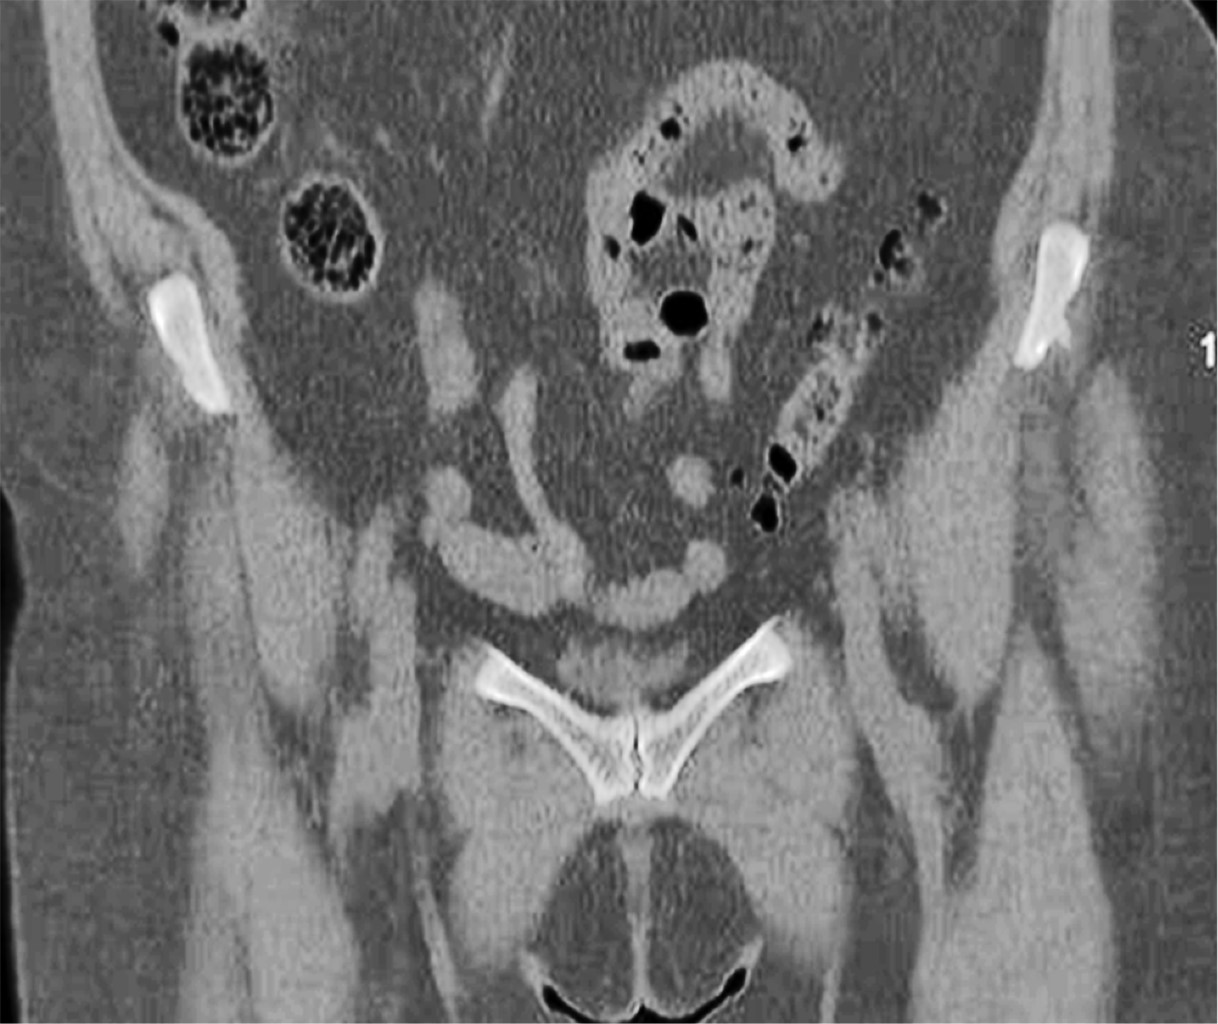

Posteriormente se solicitó una tomografía computarizada (TC) de pelvis en el que se confirmaban los cambios degenerativos (Figuras 4 y 5) y una resonancia magnética que mostraba hallazgos de inflamación en las sínfisis compatibles con osteítis de pubis, asociados a edema de la musculatura adyacente. Ambas pacientes estuvieron realizando sesiones de fisioterapia y toma de antiinflamatorios no esteroideos (AINE) y corticoides con escasa mejoría. La infiltración de bupivacaina junto con corticoide fue el tratamiento más efectivo, pero pasados los dos meses la clínica, se reprodujo y se planteó en ese momento la opción quirúrgica. Las puntuaciones en la escala visual analógica (EVA) previamente a la cirugía fueron de 8 y 9, respectivamente.

Figura 5